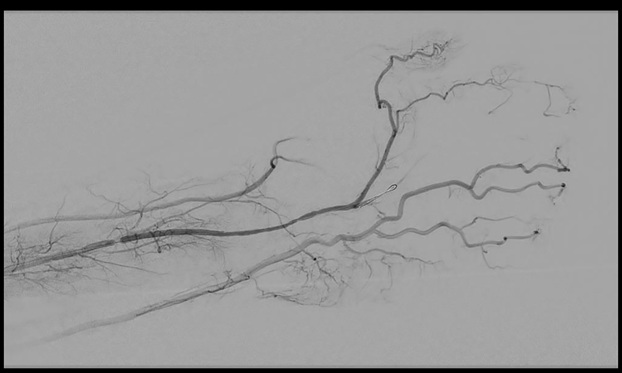

In the second procedure catheter directed thrombolysis was initiated with tissue plasminogen activator. After 14 hours of lytic therapy the patient returned to the operating room for discontinuation of lytic therapy and percutaneous transluminal angioplasty of the PMA at the level of carpal tunnel. Completion angiogram as shown in Figure 2. Post operatively his hand was pink and warm, motor and sensory were grossly intact and had no signs of ischemia. He was discharged home in stable condition. Five days later he was seen by the plastic surgeon for numbness and tingling of the left hand. After discussions with the vascular surgeon the cause of the patient’s symptoms was surmised to be from chronic compression at the carpal tunnel and would benefit from CTR. The next day the patient underwent a CTR that showed a grossly normal median nerve. Unfortunately, the carpal tunnel was not further explored and the persistent median artery was not searched for during this procedure. The patient was seen by the vascular clinic 18 days after last vascular procedure and plastic surgery clinic 11 days after CTR for postoperative visits at which time he was free of any pain or color changes to the left hand or digits. Aspirin was continued and he was taken off Clopidogrel. He was to return to the plastic surgery clinic in 6 weeks and to the vascular clinic in 6 months but has not returned the either clinic and has been lost to follow up. Institutional Review Board (IRB) approval was obtained prior to undertaking the any investigations involving the patient and case.

Figure 2. Persistent Median Artery Post Lysis. Angiogram findings of the persistent median artery now open after Fourteen hours of catheter directed thrombolysis therapy and balloon angioplasty